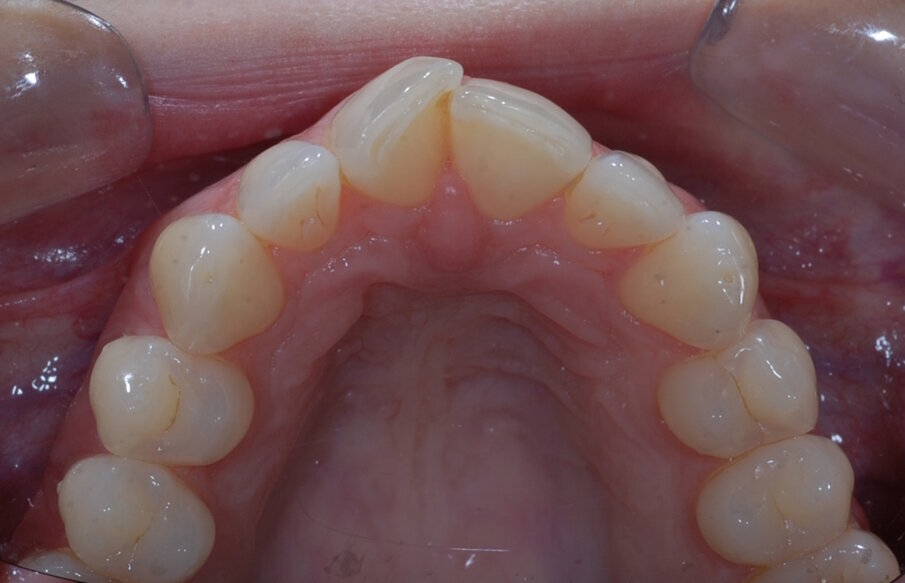

Fig. 20: Post treatment occlusal

Using the digital setup, I was able to discuss the final outcome with the patient, as well as explain the composite bonding process that would take place at the end. The treatment goal was to achieve straighter, more natural looking teeth and restore incisal wear in UR1 and UL1 while preserving the enamel. Information about the bonded retainer was also given at this time and the importance of retention. After she consented to the treatment plan, impressions were made and the appliance was ordered from the laboratory.

Fixed retainer bonded followed by composite bonding of UR1 and UL1 using the reversed Fixed retainer bonded followed by composite bonding of UR1 and UL1 using the reversed triangle technique. The benefits of this technique include: • Affordable • Ethical (preserves tooth structure) • Aesthetic • Simple • Complements alignment therapy

Afterwards, the restoration was polished with both flexi disks and Mini FlexiBuff with Enamelize polishing paste. At the end of this appointment, new impressions were taken for new bleaching trays and an Essix retainer. |